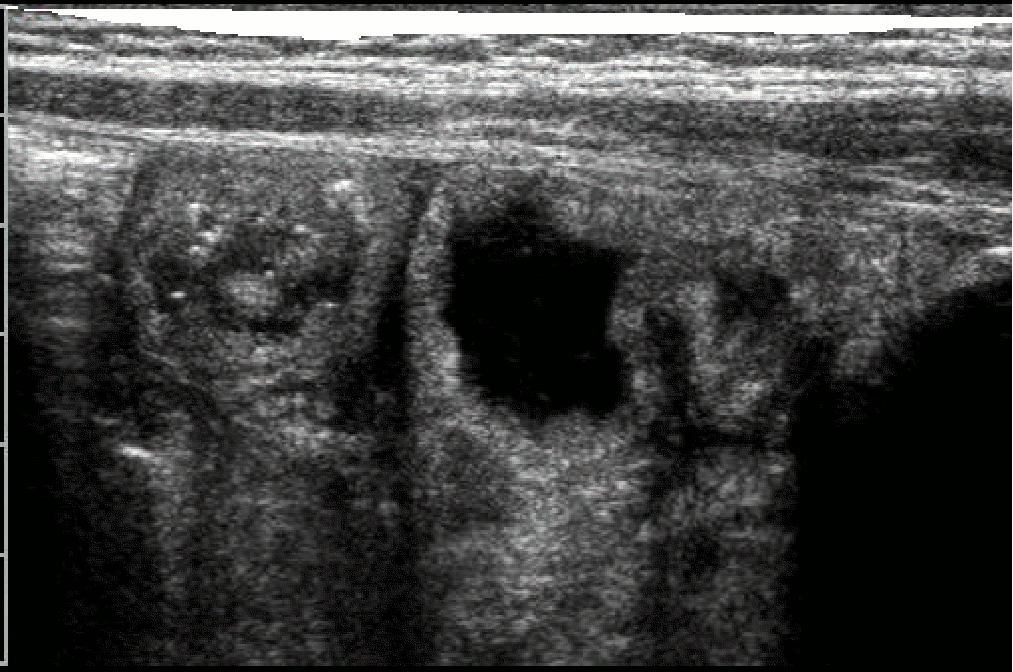

La laparoscopia esplorativa eseguita dopo assunzione orale di un pasto grasso (latte di soja) tinto con un colorante alimentare ha evidenziato diffusa trasudazione del chilo attraverso la parete intestinale. Sono risultate infine dirimenti le sezioni istologiche che hanno messo in luce l'ectasia dei vasi linfatici. (fig. 4)